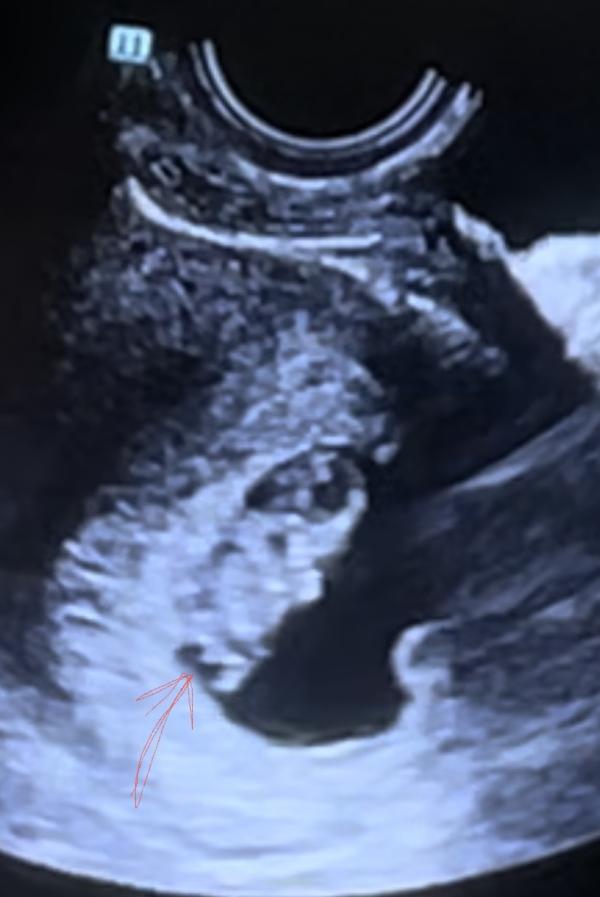

Девочки,это же хвостик ?🤣ну невозможно же на 10 неделе узнать пол

На таком сроке клитор и писюн выглядят одинаково. Так что увы) даже если это половые органы ,то точно вам никто не скажет чьи , мужские или женские)

Я не думаю что это мужской пол так как пол у плода формируется к 9 неделям.А тут 10 недель и так четко все видно,ну такое себе,сомнительно если честно.У нас на первом скрининге не видно было,в 14 недель предположили и в 20 подтвердили точно.Сказали что на первом скрининге это так предположительно только могут сказать.а дальше либо подтвердить либо нет